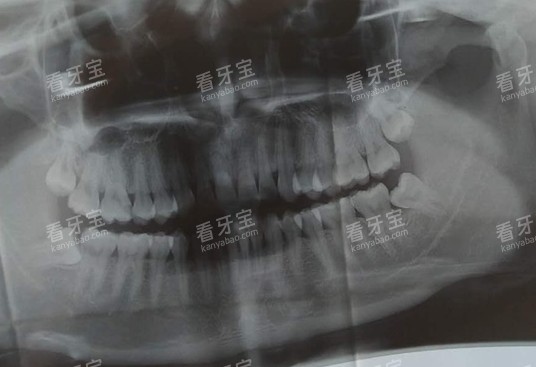

设备方面,诺贝尔口腔投入超2000万元引进了一批高端设备,像德国西诺德3D口腔CT、美国NEWTOM口腔CT、显微根管治疗仪等,这些设备能帮助医生更比较准地定位根管,让治疗过程更精细,减少对牙齿的损伤。而且他们采用不痛根管治疗技术,治疗时几乎没什么痛感,深入打破了“根管治疗很疼”的固有印象。

在根管治疗方面,柏乐口腔的优势在于价格透明、梯度合理,能满足不同预算人群的需求。根据2025年更新的价格表,前牙根管治疗280元起/颗,适合单根管前牙病变,治疗周期大概3次;双尖牙根管治疗700元起/颗,针对双根管或三根管的前磨牙病变;后牙根管治疗(3根管)900元起/颗,操作难度相对较高,周期也会稍长一些。如果是复杂病例,比如根管弯曲、钙化,需要做显微根管治疗,后牙价格1800元起/颗,精细度更高,治疗结果更有因素。